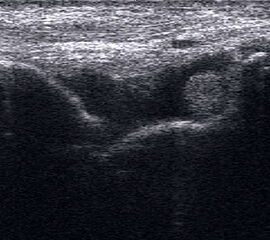

Ruptur Lig. fibulocalcaneare

Längsschnitt über dem Lig. fibulocalcaneare. Die Peronealsehnen erscheinen als echoreiche runde bis ovaläre Struktur.

Abbildung 19

Lagerung: Rückenlage, OSG in Neutralstellung.

Schnittebene: LS über Lig. fibulocalcaneare.

Referenzstrukturen: Fibulaspitze und Talus.

Befunde: Das Lig. fibulocalcaneare is nativ schlecht abgrenzbar, da es in die Tiefe und nicht parallel zum Schallkopf verläuft. Direkt über das Band ziehen quer getroffen die Peronäussehnen. Durch die Distorsion kann auch das Peritendineum peroneale einreißen. Die Peronealsehnen sind dann in ihrer Sehnenscheide von Blut umgeben, was sich als echoarmer Ring (Halo-Phänomen) darstellt und ein indirektes Zeichen für eine Verletzung des Lig. fibulocalcaneare ist.